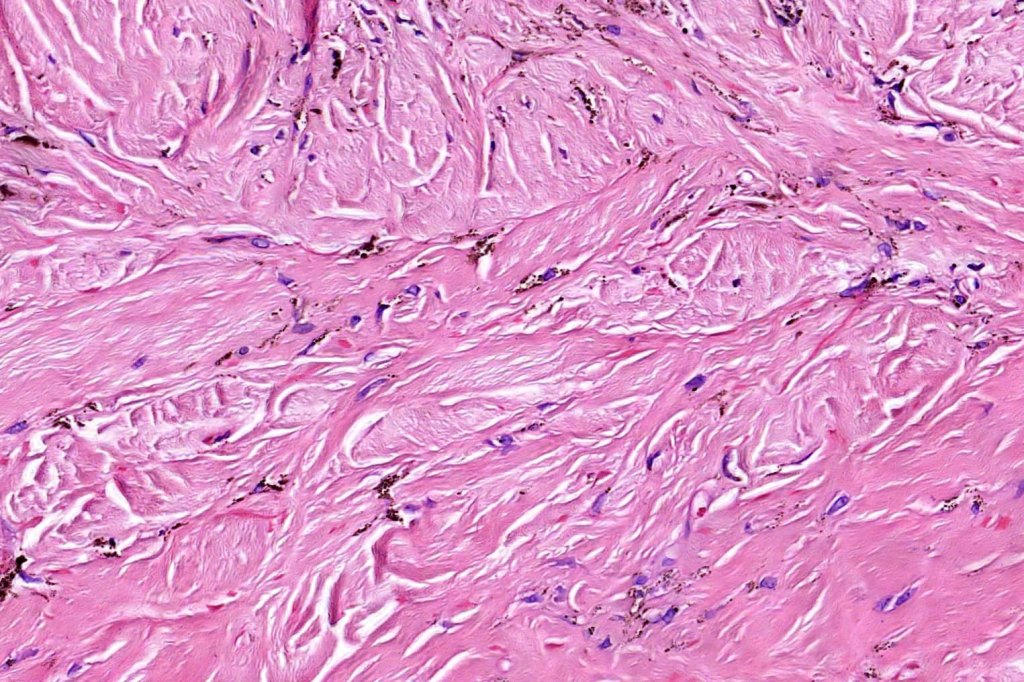

Histologically, it is characterized by a dense population of spindled, dendritic melnanocytes & melanophages with variable fibrosis. It may sometimes represent a component of a combined nevus. Mitotic activity is not usually present and pleomorphism is absent (see atypical blue nevus below). Involvement of the arrector pili muscle is not uncommon.

•Stromal fibrosis, myxoid change, vascular hyalinization with cyst formation are often seen

•Desmoplastic variant